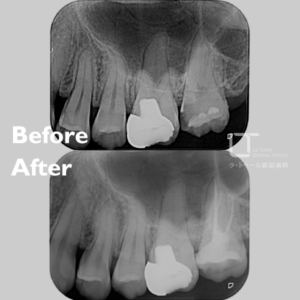

精密根管治療・40代(女性)|「他院治療後も違和感が続く歯を静脈内鎮静下で精密根管治療」

治療方法 精密根管治療、静脈内鎮静法 施術費用 ¥209,000(静脈内鎮静込み) 通院回数 1回 通院期間 メリット 感染した神経や組織を除去して痛みの原因を取り除き、ご自身の天然歯を残せる可能性を高めます。周囲組織への悪影響を抑えることが期待できます。 リスクと副作用 精密根管治療、静脈内鎮静法は保険適用外です。精密根管治療後には痛みや違和感が続くことがあり、歯が脆く割れやすくなる場合があります。感染が除去できなかった場合は再発のリスクがあります。 精密根管治療の治療例です。「以前、他院にて治療した歯の違和感が改善しない。歯科治療が得意ではないため、 […]